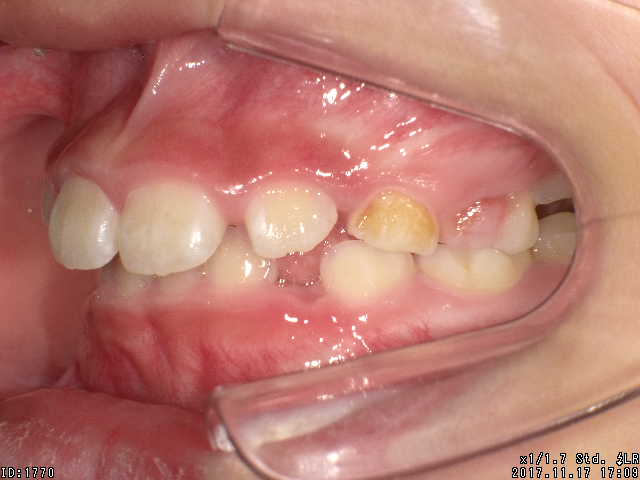

矯正前

| 症状 | 上顎前突 過蓋咬合 |

| 通院時の 年齢 |

8才1ヶ月〜15才10ヶ月 |